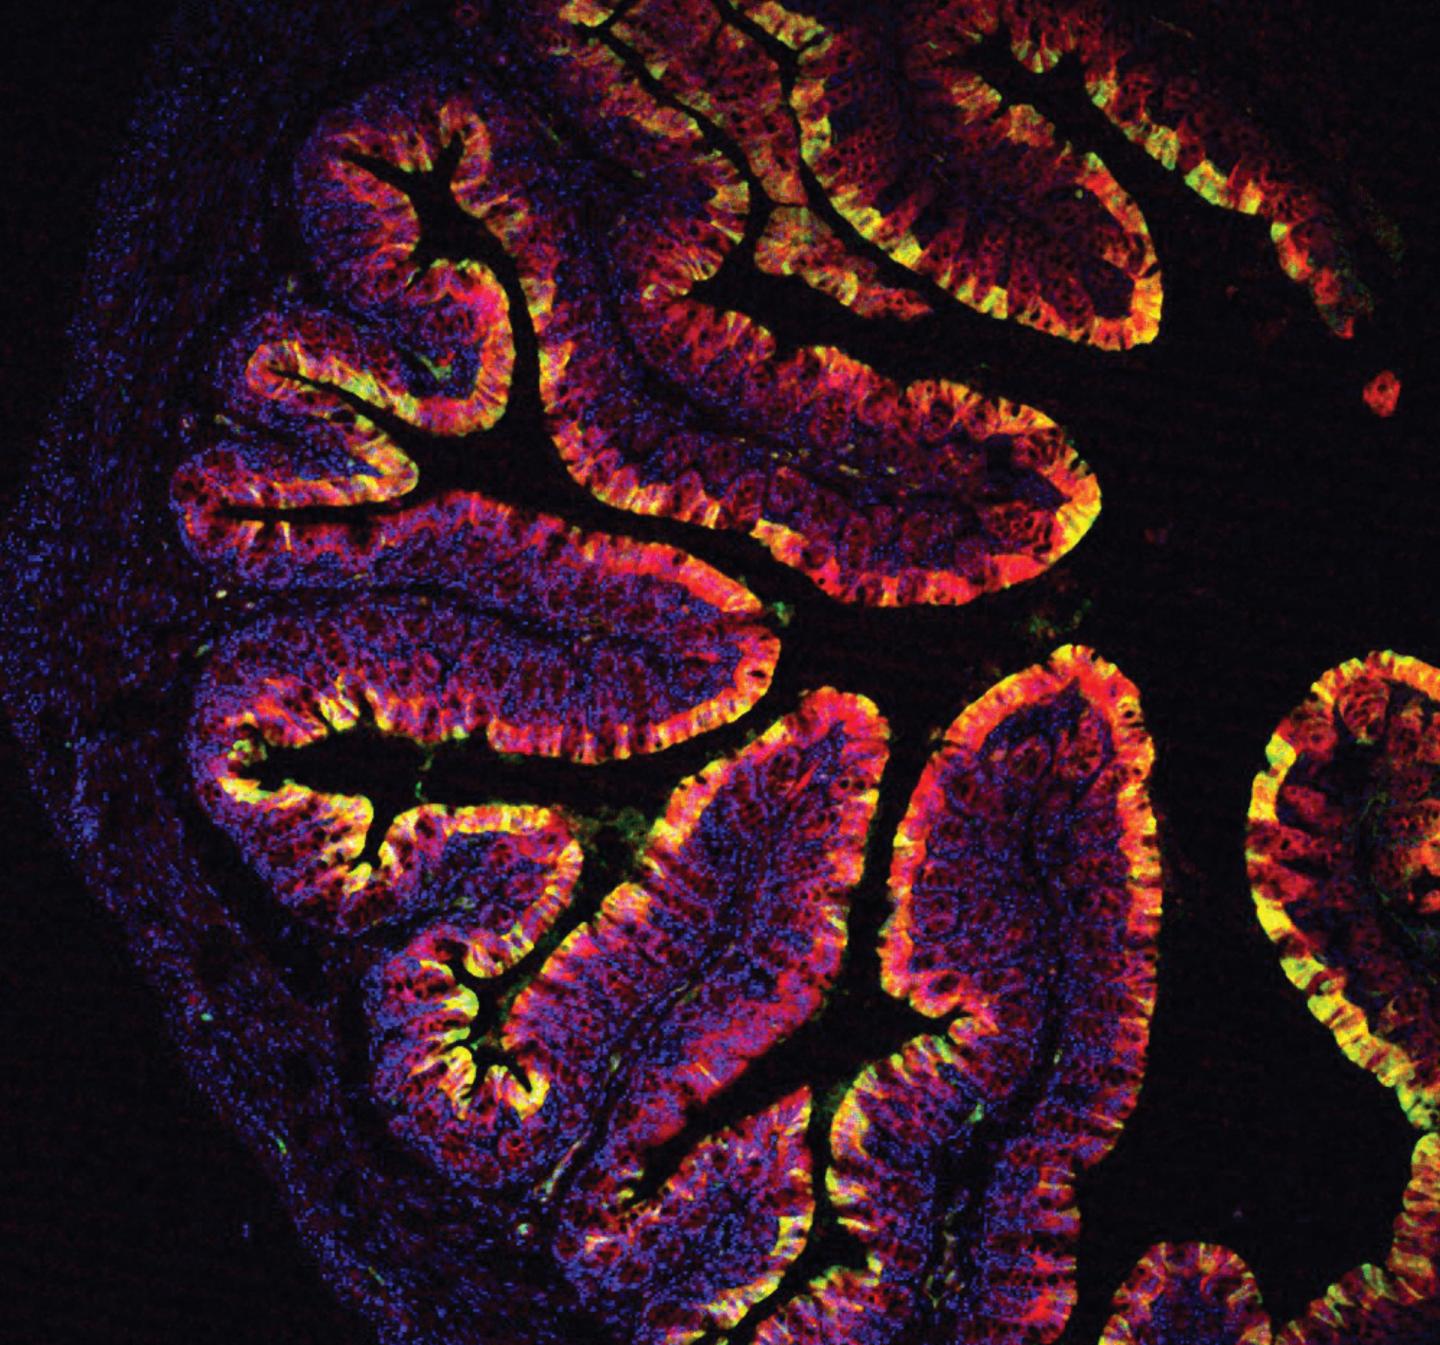

Mouse Colon

image: This is a mouse colon from Cyp1a reporter mice after feeding with I3C. view more

Credit: Chris Schiering, Francis Crick Institute